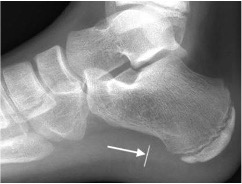

Gout

- Hyperuricaemia causes deposition of urate crystals

- First metatarso-phalangeal joint is commonly involved, termed a podagra

- Well-defined erosions with sclerotic borders which have a ‘punched out’ or ‘rat bite’ appearance and overhanging margin

- Joint space and bone density are preserved until late in the course of the disease

- Urate crystals deposited in the soft tissues form tophi and periarticular lobulated soft tissue masses

- Chondrocalcinosis may represent deposition of calcium pyrophosphate dihydrate (CPPD) crystals (pseudogout)

Gout of first MTP joint with well defined ‘punched out’ erosion with overhanging margin (arrow) and soft tissue swelling (arrowheads)